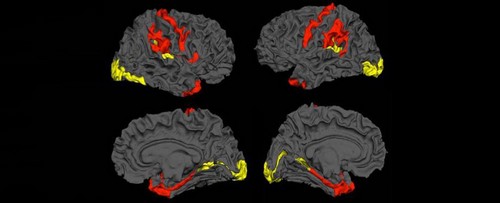

Following 98 patients with schizophrenia and 83 without, the team used MRI technology and a special method called “covariance analysis,” to distinguish the increase of brain tissue. This is the first time such a method has been used to prove the brain’s ability to reverse the illness’ effects, and opens doors to possible cures.

“Our results highlight that despite the severity of tissue damage, the brain of a patient with schizophrenia is constantly attempting to reorganize itself, possibly to rescue itself or limit the damage,” Palaniyappan said.